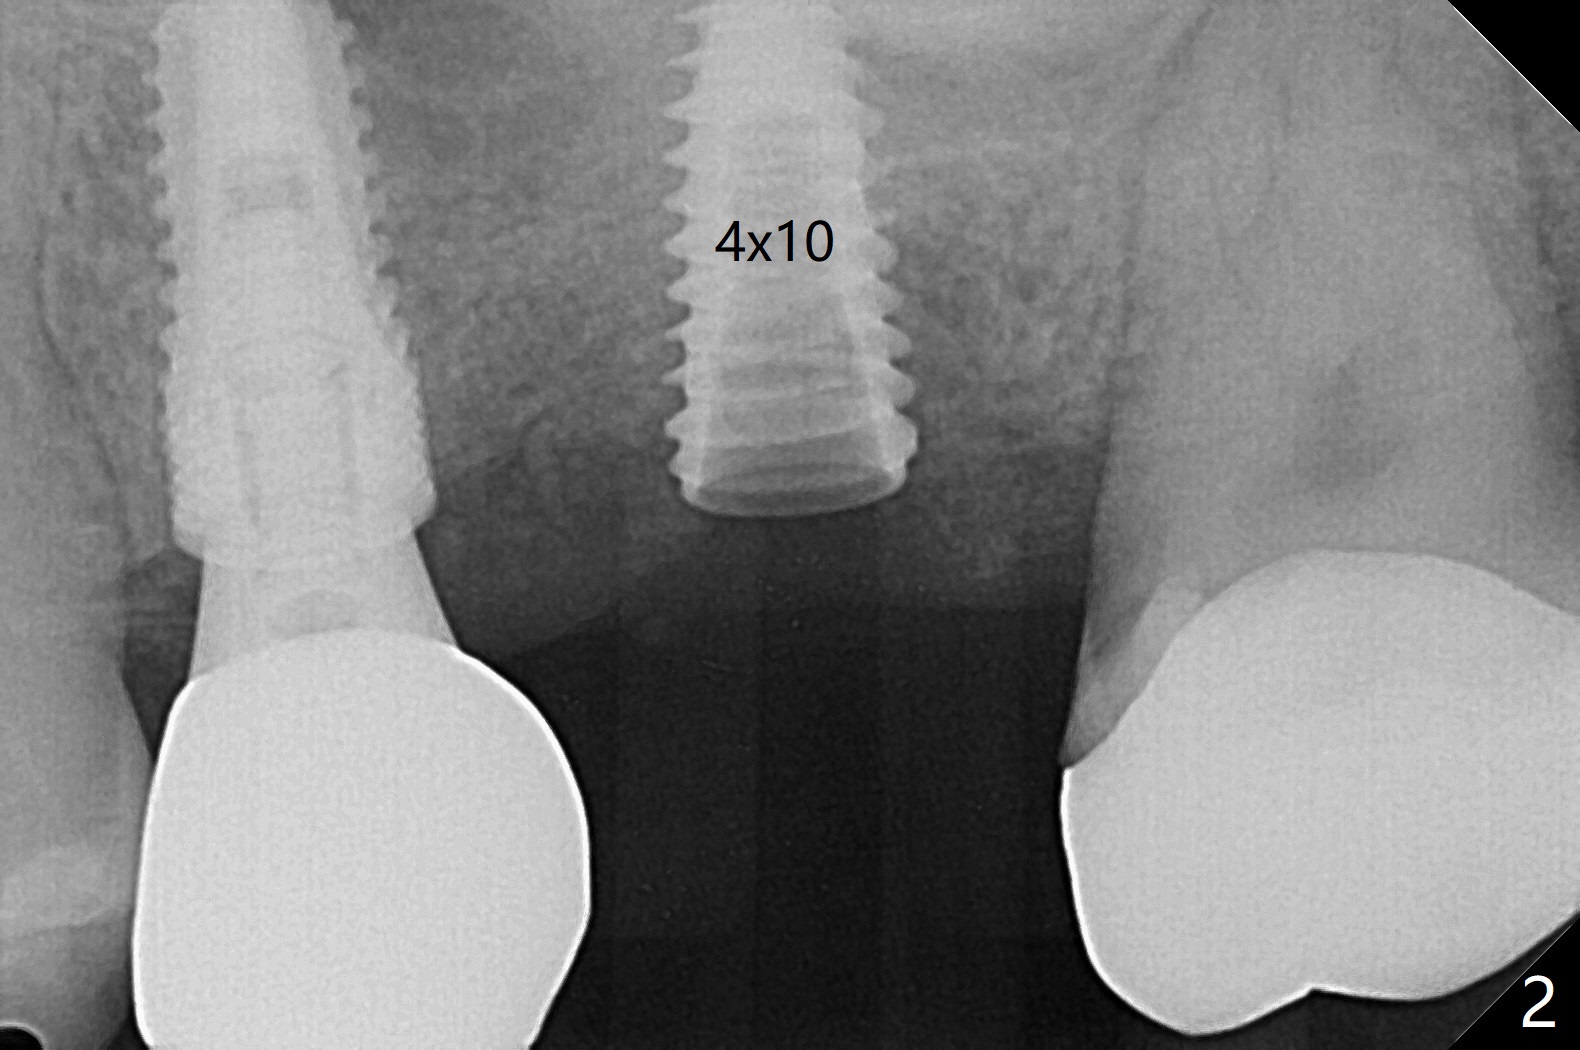

60岁男,左上6(牙根折裂严重骨质吸收)位点保存后6个月,回来植牙。术前CT显示骨质密度低,宽度足够,角化龈也宽,前后牙齿都有牙冠,制作导板麻烦,所以采纳徒手种植。使用4毫米活检打孔刀(Biopsy Punch)进入,简化手术,但是又怕开口不正,不敢用大号植体,术后CT发现钻洞偏颊侧。针对骨质密度低,使用1.2毫米钻头后(约8毫米),使用旋转式骨扩张器直至2.4/3.7毫米(图一(红虚线:原来骨质缺损)逐渐增加深度至11毫米),备洞几乎没有失去骨质,钻洞周围骨质密度谅必增高),取出最后一个扩大器后发现上颌窦底板破裂,放置粘性骨粉,使用4毫米报废植体做上颌窦提升,重复一次(图二,三),稳定性尚可。再次放置骨粉和PRF膜,使用正式植体提升(4.5x8毫米),临床上很难判断是否植体植入牙槽嵴之下(可能骨质疏松),只好拍摄CT(图四,五),好像正好牙槽嵴下,不过又植入骨粉一些(图七:*)。植体扭力~15Ncm,保险起见,放置愈合帽,表面放置少许骨粉以及打孔留下的牙龈(图六:G,之前一直泡在PRF上清液里),牙周胶水固定游离牙龈以及牙周敷料保护。术后6小时没有鼻出血。所以骨质缺损严重,植骨后,虽然缺损外形得到恢复,但是骨头质量,固定植体能力还不够。植牙时,需要适当改变手段,例如使用骨凿,提高骨质密度,而不是单纯使用钻头。术后病人恢复正常,没有疼痛,六天复诊,牙周敷料已经脱落,打孔的牙龈附着颊侧,部分骨粉暴露,但是看样子挺稳定,好像游离牙龈必须缝合。使用树脂敷料牢靠些。术后五周,伤口基本愈合,一处未愈合,与下面骨粉相通,用牙周探针稍微搅动,出血(图九)。擦干血迹,伤口还不错(图十)。术后2个月伤口好像正常愈合(图十一)。术后4.5个月根尖片显示6种植比5深,往后螺纹暴露可能性减少(图十二)。